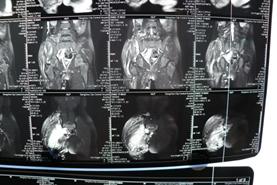

经过检查发现小诺右侧臀部及大腿有大面积的淋巴畸形,右小腿、右足踝部及右足底也有许多弥散性的肿块,不仅病变部位多且侵犯严重,加上之前已经做过三次手术,这次的手术对于医生而言无疑是巨大的挑战!经过前期充分的准备,小诺的手术如期进行,从上午10点50一直到晚上11点,历时整整12个小时,终于顺利完成手术,术中发现病变累及大面积的正常肌肉和多处神经,乔主任巧妙的采用切除和微创相结合的方式治疗病变部位,仔细分离重要的血管和神经,将大面积的病变全都切除。术后小诺身体恢复情况很好,目前正在一步步的康复,迎接她的是健康和快乐的明天!